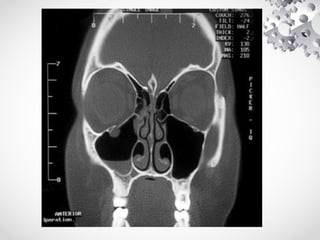

Radiological investigations:

1. Plain xray nasal bones

2. Xray paranasal sinuses water's view

3. CT scan paranasal sinuses - This is a must in all cases of class

II and class III fractures of nasal bones for precise estimation of

damage.